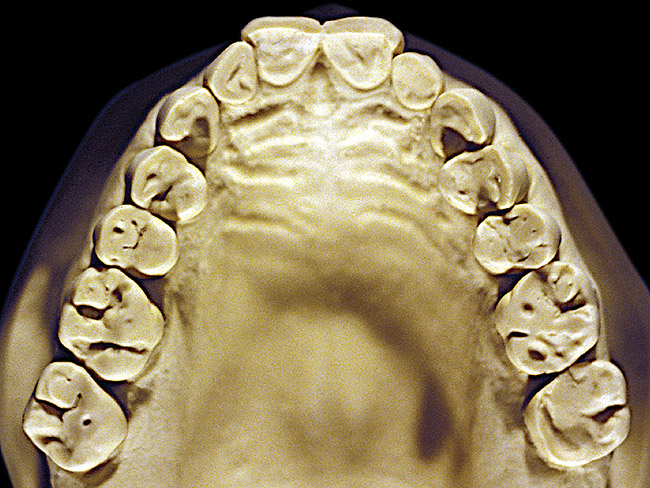

Figure 7  Moderate NCLTS from toothpaste, maxillary arch.

Figure 7

Figure 7 and Figure 8 are examples of NCLTS resulting from toothpaste. Upon examination, one could see that the overall anatomical detail of the teeth was faded with a sandblasted appearance. A closer view of the facial surfaces (Figure 9 and Figure 10) illustrates this to a greater degree and one can observe that the normal intricate facial anatomy was completely missing. It is interesting to note there was no cervical recession of the gingiva, even though every surface of every tooth had been abraded. This is due to the fact that this patient had always used a soft, round-ended filament toothbrush.21-22 This patient's sole desire regarding her oral hygiene was to get her teeth whiter.

So that the previous example is not misleading, the behavioral profile of the toothpaste abuser is not necessarily the "caries-free immaculate oral hygiene patient," but can be virtually anyone who brushes their teeth with toothpaste. Figure 11 and Figure 12 illustrate a more advanced example of toothpaste abuse showing a patient with multiple restorations and some unkempt teeth. The anatomical details were faded with a sandblasted appearance and the silver alloy restorations were highly polished. The facial surfaces of the mandibular canines and premolars were affected the most, creating the pathognomonic pattern. Figure 13 and Figure 14 are a close-up view of this area, illustrating a cupping or cratering effect, but of the asymmetrical variety. This patient did not like the color of his teeth and spent an inordinate amount of time brushing his teeth. Again, likewise due to the exclusive use of a round-ended, soft-bristle toothbrush, note there was no cervical gingival recession in this case either. When the featured casts illustrating toothpaste abuse (Figure 7, Figure 8, Figure 9, Figure 10, Figure 11, Figure 12, Figure 13 and Figure 14) were hand-articulated, the worn surfaces did not match up and the diagnosis of toothpaste abuse was confirmed.